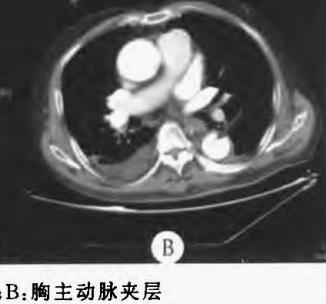

动脉夹层是急症中的急症,随时有生命危险,增强CT诊断动脉夹层一般不难。主动脉夹层常表现为突发的剧烈胸背或腹部撕裂样疼痛,常伴血压升高,但是部分患者症状不典型,甚至没有疼痛感,掌握CT平扫对动脉夹层的诊断价值,有时候可尽早发现潜在的巨大危险!

仔细一看,主动脉里面有线样高密度阴影!这个要高度警惕主动脉夹层!

图5

增强CT一看,吓到一大片!太惊悚了!

图6